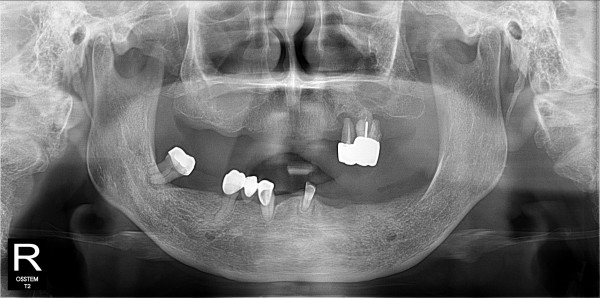

네비게이션 임플란트 최고관리자 0건 23-11-07 18:39 본문 풀케이스 네비게이션 임플란트 목록 이전글네비게이션 임플란트 23.11.07 다음글네비게이션 임플란트 23.11.07 댓글목록 0 댓글목록 등록된 댓글이 없습니다.